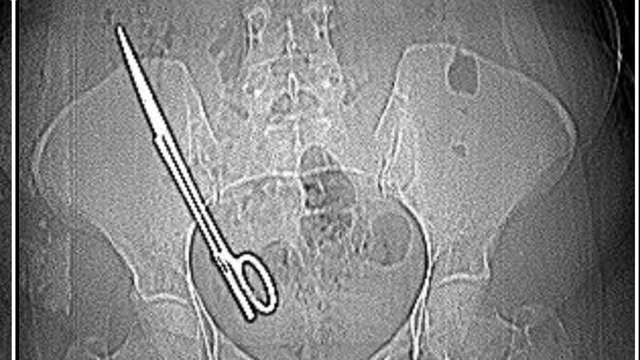

Kahramanmaraş'ta baş ağrısı şikayetiyle hastaneye giden Fatma Kala'nın (36) karnında 16 santimetre uzunluğunda ameliyat makası tespit edildi. 7 yıl önce geçirdiği kist ameliyatı sonrası karnında makas unutulduğu ortaya çıkan Kala, ameliyatı yapan doktor hakkında savcılığa suç duyurusunda bulunduğunu belirterek, "Hep haberlerde duyuyordum böyle olayları, ameliyatta sargı bezi, iğne aynı şeyin daha fazlası başıma geldi maalesef. Ben 7 yıl boyunca mucize eseri hayatta kalmışım" dedi

İddiaya göre; Koray Ş., 7 yıl önceki ameliyattan dolayı bir komplikasyon oluştuğunu ve acilen ameliyat etmesi gerektiğini söyledi. Doktorun tavırlarından şüphelenen Fatma Kala, ameliyat olmayı reddedip KSÜ Sağlık Uygulama ve Araştırma Hastanesi'ne gitti. Burada yapılan tetkiklerde Kala’nın karnında 16 santimetre uzunluğunda makas olduğu tespit edildi. Ameliyatla karnındaki makas çıkarılıp sağlığına kavuşan Fatma Kala, hastaneden çıktıktan sonra avukatı aracılığıyla 7 yıl önce ameliyatı gerçekleştiren doktor Koray Ş. hakkında Kahramanmaraş Cumhuriyet Başsavcılığı’na suç duyurusunda bulundu.

Baş ağrısı şikayetiyle gittiği hastanede doktorların 'Karnında makas var' deyince şoke olduğunu belirten Fatma Kala, 2017 yılında kist ameliyatı olduktan sonra iç kanama geçirdiğini ve tekrar ameliyata alındığını, makasın da o ameliyatta unutulduğunu söyledi. Karnında makas varken küçük çocuğu ile birçok defa MR odasına girdiğini belirten Kala, “Bundan 7 yıl önce özel bir hastanede ameliyat oldum. O günün gecesinde tekrar iç kanama geçiriyorum ve ikinci ameliyatımı oluyorum. Bu ameliyatta maalesef ameliyat olan bölgemde ameliyat makası unutuyorlar ve biz bunu 7 sonra öğreniyoruz. Baş ağrısından dolayı hastaneye gittik. Hastanede doktorumuz MR'a girmem gerektiğini söyledi. Ben MR teknisyenine daha önce çocukla beraber MR odasına girdiğimde benim sağ tarafımda çekme olduğunu söyledim.

Teknisyen bana 'Bu şekilde seni MR'a alamam, çok tehlikeli. Acilen ameliyat olduğun doktoru bul' dedi. Doktorumuz bizi hemen röntgene aldı. Röntgende bir yabancı cisim görmüş ama bize söylemedi, ‘Daha önceki ameliyatından dolayı bir komplikasyon oluşmuş. Seni ameliyat edip dedi o komplikasyonu ortadan kaldırmam gerekiyor’ dedi. Biz doktorun telaşlı tavrından şüphelendik. Eşimle birlikte tıp fakültesine gittik. Oradaki acil doktorlarına başımızdan geçen olayı anlattık. Onlar beni röntgene soktu. Oradan ilaçlı tomografiye girince daha önceki ameliyatımda bırakılan makas orada görüldü. Genel cerrahi bölümünde bu makas çıkarıldı'' diye konuştu.